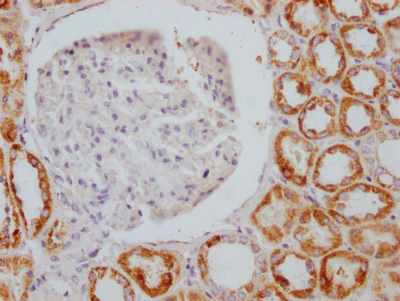

IHC image of CSB-RA296617A0HU diluted at 1:100 and staining in paraffin-embedded human kidney tissue performed on a Leica BondTM system. After dewaxing and hydration, antigen retrieval was mediated by high pressure in a citrate buffer (pH 6.0). Section was blocked with 10% normal goat serum 30min at RT. Then primary antibody (1% BSA) was incubated at 4℃ overnight. The primary is detected by a Goat anti-rabbit IgG polymer labeled by HRP and visualized using 0.05% DAB.